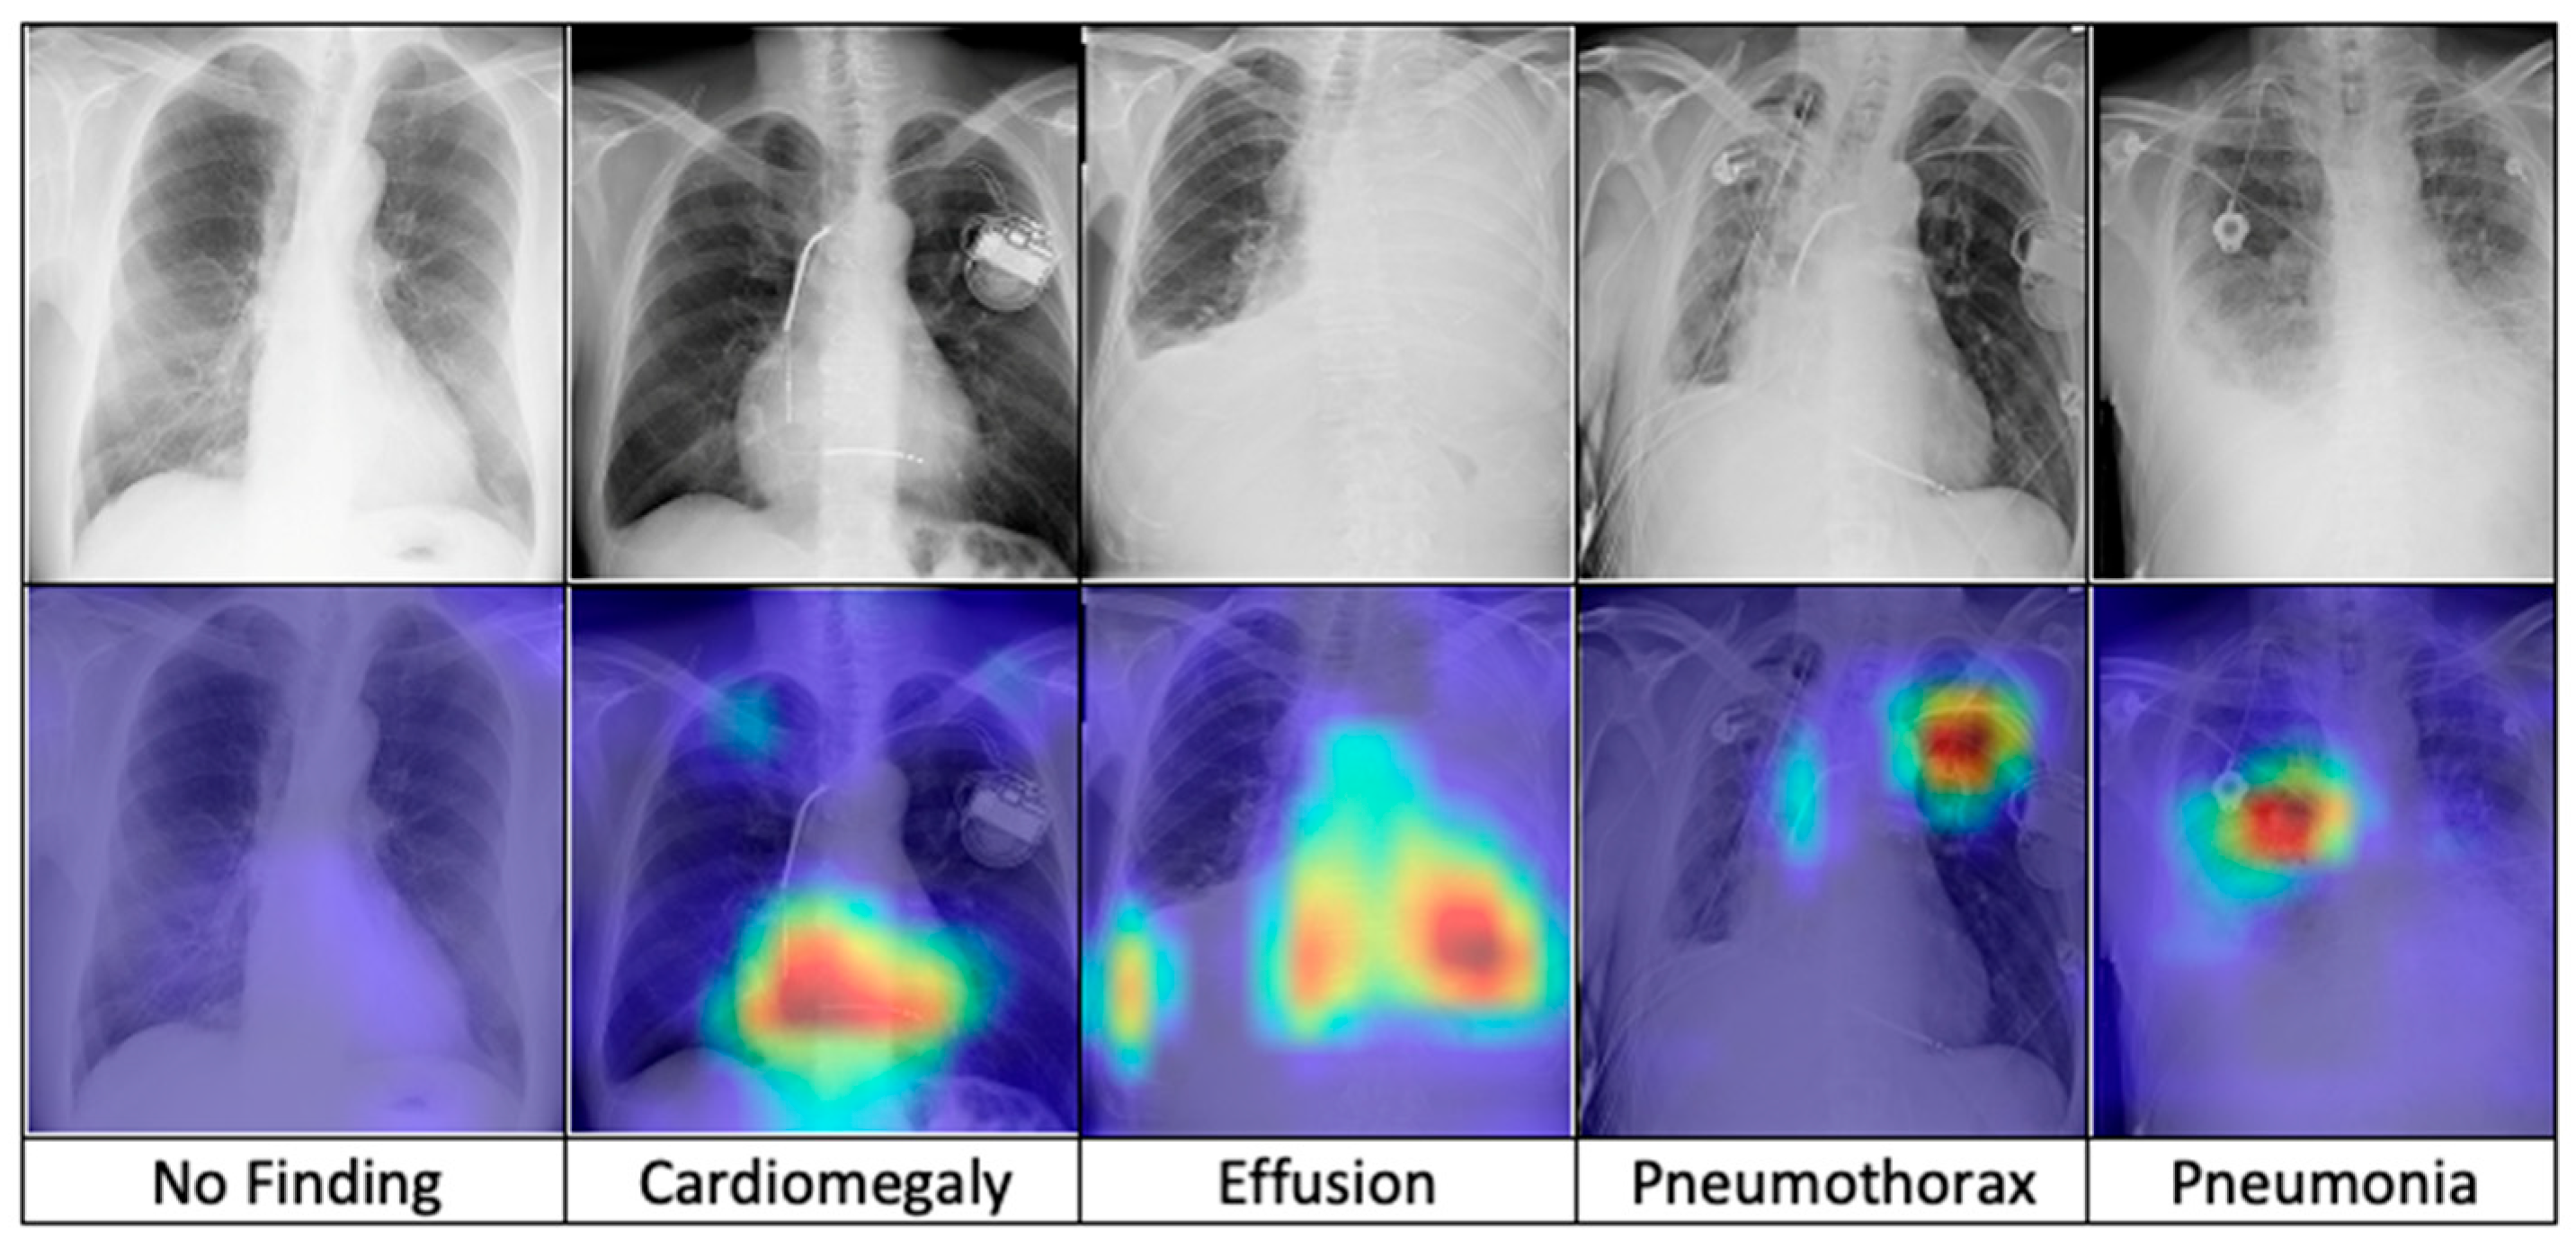

After training, the model is combined with the Grad-CAM algorithm to generate saliency maps for the test images. These maps are overlaid on the original chest X-ray images to visualize class-discriminative regions, highlighting the areas that are most influential in predicting the five diagnostic categories. Figure 7 presents a comparative visualization of the resulting heatmaps across cardiomegaly, effusion, pneumothorax, pneumonia, and no finding.

Figure 7.

The comparison of heatmaps among five categories of chest X-ray images selected for classification.

The superior performance of the FSRFNet50 model can be primarily attributed to its sophisticated architectural design, which efficiently handles the inherent variability of X-ray imaging data. While high performance metrics are important, model interpretability is equally critical in medical applications. To enhance transparency, we employed Grad-CAM to visualize the regions of X-ray images that the model emphasizes during prediction. These visualizations offer insights into the model’s decision-making process, supporting both clinical relevance and model refinement. Our experiments showed that incorporating interpretability techniques not only improved understanding but also contributed to optimizing model accuracy. As seen in Figure 7 (from left to right), the Grad-CAM heatmaps demonstrate the interpretability of the proposed RadAI model across various thoracic pathologies. For normal cases, no significant regions are activated, aligning with the “no finding” prediction. In cases of cardiomegaly, the heatmap highlights the enlarged heart region, while pleural effusion is accurately localized in the corresponding X-ray images. For pneumothorax, strong activation is observed in the left lung area. Although pneumonia cases are more complex due to diffuse patterns, the heatmap still reveals high-probability regions, supporting the model’s classification. These visualizations not only validate the model’s ability to localize disease-relevant features effectively, but also help the radiologists to analyze the activated region effectively.